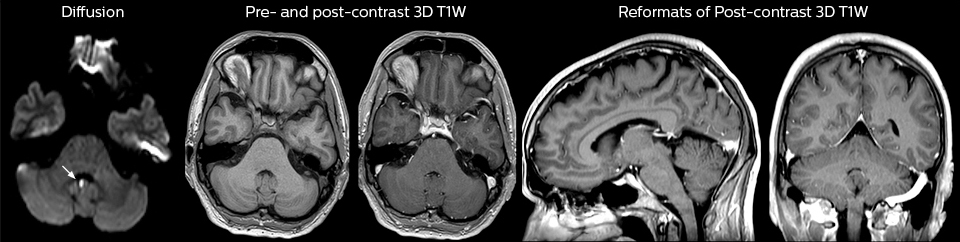

Eine Reihe von Protokollen wurde ausgearbeitet, um sicherzustellen, dass überweisende Ärzte die am besten geeignete MRT-Untersuchung anfordern. Die optimierten MRT-Protokolle umfassen auch die kontrastmittelverstärkte 3D-Bildgebung, die es den Neurochirurgen ermöglicht, während eines stereotaktischen Eingriffs im OP komfortabel auf die isotropen Daten zuzugreifen.